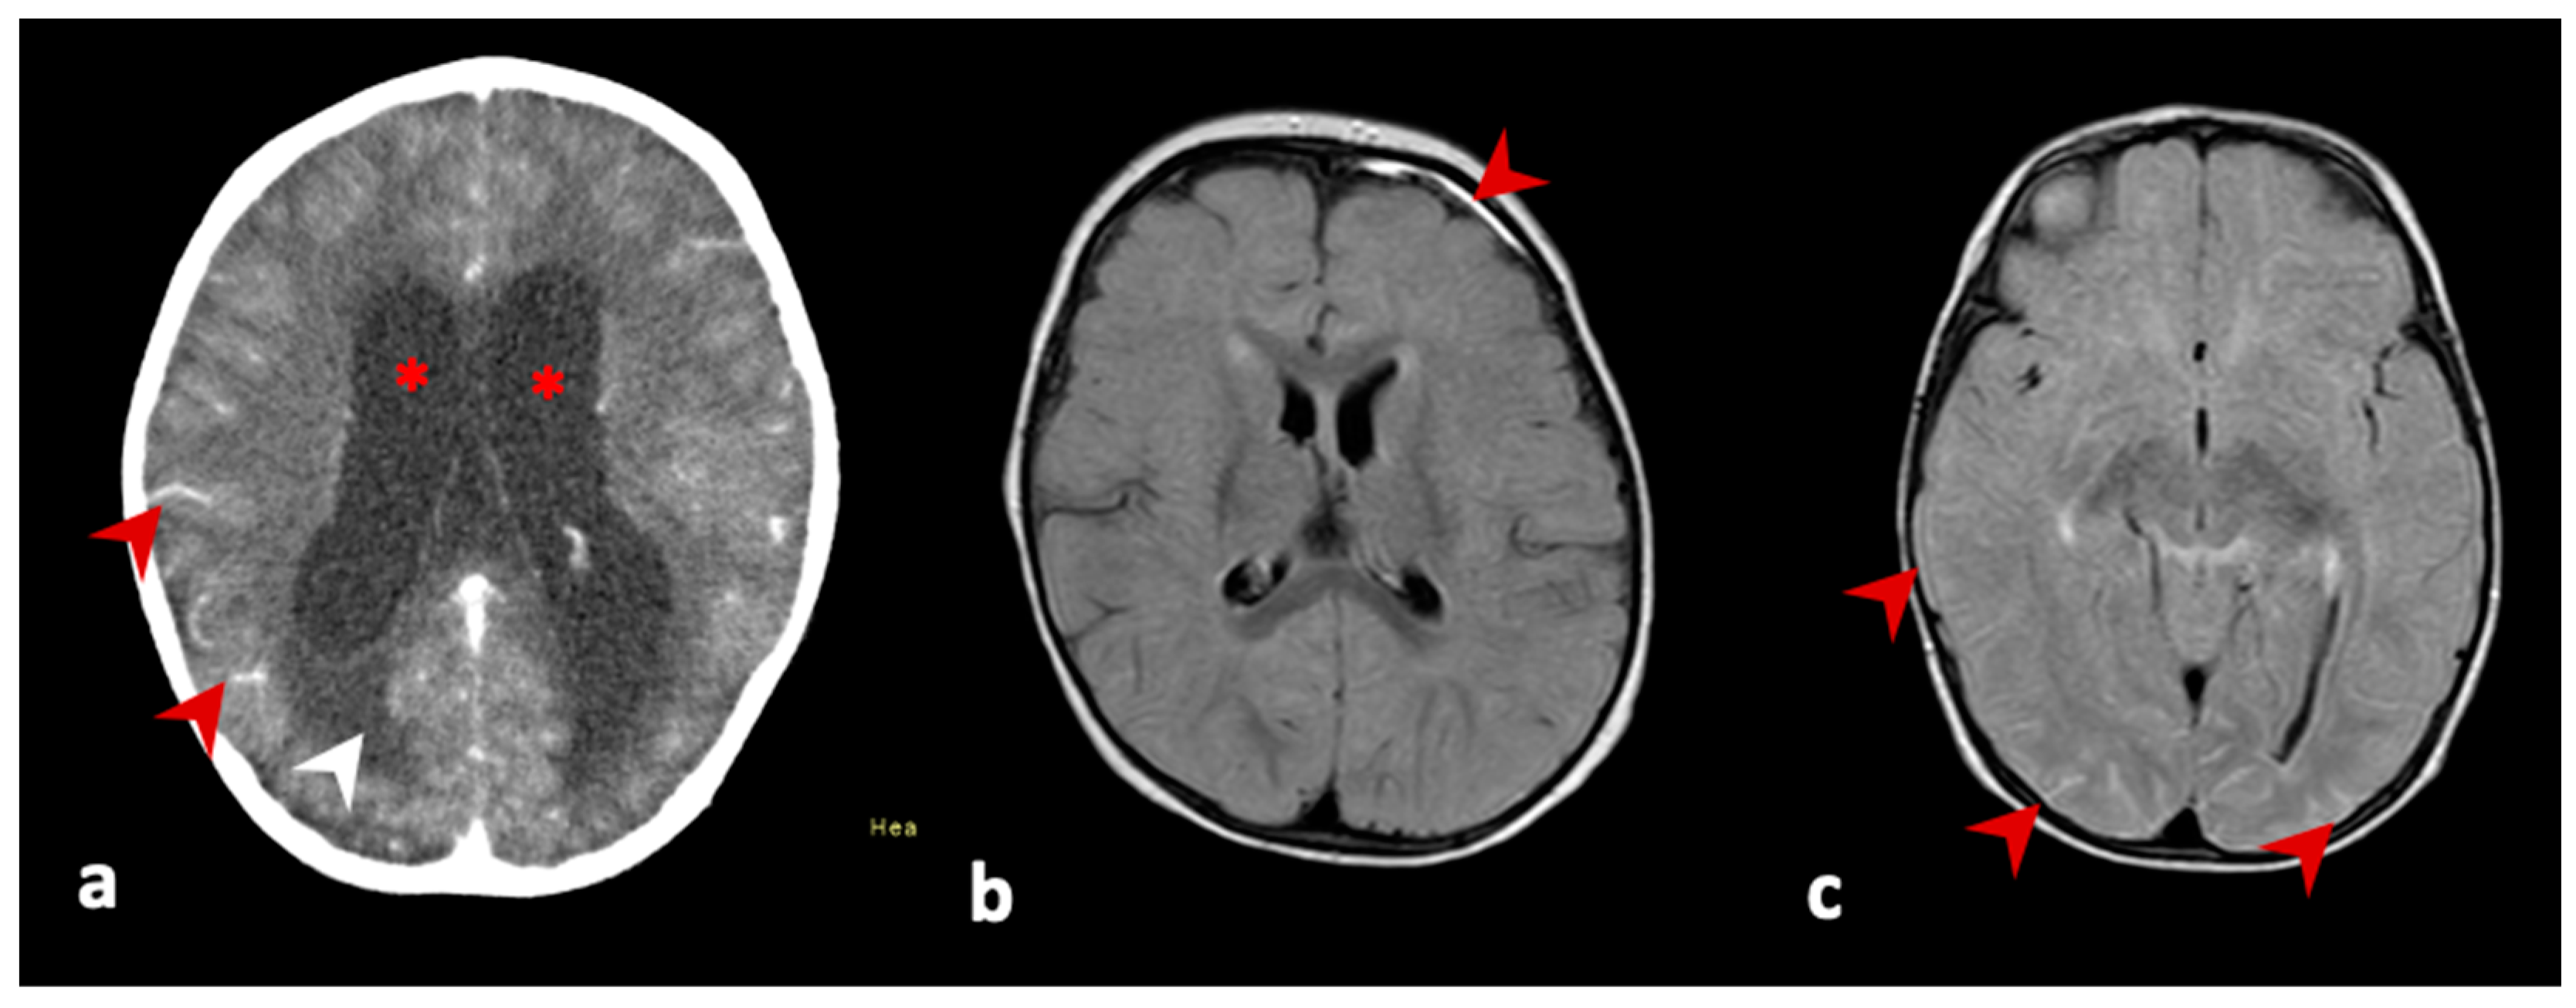

| 1; | female, 4 years of age | 20 July 2021, second dose | 25 August 2021 | 36 days | vomiting, hyporexia, non-responsiveness, weight loss of 3 kg, bradypnea, bradycardia. outcome: follow-up on 12 November 2021, no recurrence of signs and symptoms, without sequelae | leukocytes 17 cells/mm3, lymphocytes 86%, neutrophils 0%, protein 153 mg/dL, glucose 37 mg/dL, culture negative | brain CT: signs of hypertensive hydrocephaly (supra and infratentorial). brain NMR: increased dimensions of the ventricular system, with ependymal transudation and interstitial edema, in addition to hyperdynamic flow within the third and fourth ventricle and mesencephalic aqueduct. Note leptomeningeal enhancement in the base cysteines and cranial pairs. brain biopsy: granulomatous chronic inflammatory process with focal necrosis and histiocytes | plasma/serum: Ht 33.2%; Hb 11.8 g/dL; plat 304,000/mm3; leuko: 8810/mm3; 24.9% neutro; TB: 0.22 mg/dL; DB: 0.1 mg/dL, Cr: 0.4 mg/dL; AST: 21 UI/L; ALT: 11 UI/L; GGT: 10 UI/L; AP: 112 UI/L; INR 1.17; anti-CMV IgM negative and IgG positive; PCR for CMV: negative; anti-HIV I/II: negative; anti-Rubella IgM negative and IgG positive; FTA-abs negative; anti-toxoplasmosis IgM negative; anti-measles IgM negative; anti-EBV IgM negative; anti-HSV I/II IgM negative CSF: real-time PCR TB negative; anti-dengue IgM negative; anti-Zika IgM negative; anti-SLEV IgM negative; anti-WNV negative; anti-ROCV IgM negative; anti-CHIKV IgM negative | anti-YFV IgM positive in CSF |